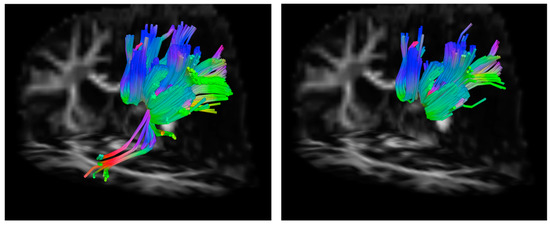

In subject 1, the difference in the number of streamlines generated between each pair of ROIs when seeding in WM ROIs compared to GM ROIs is much larger than the difference in the number of voxels between WM ROIs and GM ROIs after FA thresholding. Furthermore, a greater number of streamlines were generated between the left inferior parietal lobe and left superior parietal lobe when seeding in the left inferior parietal WM ROI, which contained a greater number of voxels after FA thresholding than the left inferior parietal GM ROI (see Table 4). Figure 3 shows a comparison of the tracts generated between the left inferior parietal lobe and left superior parietal lobe using GM and WM ROIs in subject 1. Qualitatively, the streamlines that form the tract between each of these ROI pairs traverse highly similar paths regardless of whether seeding was performed in the left inferior parietal WM or GM ROI. In subject 2, with the exception of the entorhinal cortex, fewer voxels in each WM ROI is associated with a greater number of streamlines generated between that WM ROI and the chosen target ROI. Similar to subject 1, the magnitude of the volume difference between WM and GM seed ROIs is smaller than the magnitude in the difference in the number of streamlines generated between the seed and target region. This suggests that seed ROI volume (determined in part by FA-thresholding) has an effect on the number of streamlines generated but that other factors are involved. The data from these two subjects demonstrate that there is a complex relationship between ROI shape, ROI location, individual anatomy, and the number of streamlines generated between two ROIs.

Figure 3.

Example of streamlines generated from a WM seed versus a GM seed. (left) Streamlines generated from the WM left inferior parietal ROI. (right) Streamlines generated from the GM left inferior parietal ROI. The greater number of streamlines generated from the WM seed region is clear. Additionally, streamlines that connect part of the inferior parietal ROI to the superior parietal ROI that are not captured when seeding in the GM ROI are shown. GM: gray matter, ROI: region of interest, WM: white matter.